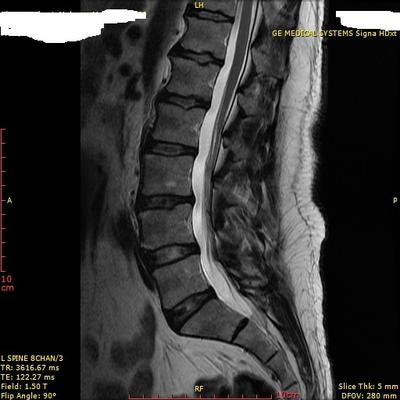

A few days ago I took an x-ray and MRI. I am uploading a few of the results. I have not received the reports yet. Meanwhile after educating myself I suspect that I am probably suffering from Cluneal Nerve Entrapment. The exact location of the tender points are about 8-9 cm to each side of the mid-line on the upper part of my buttocks. When I do a heavy duty task, the pain spreads around, my muscles become very stiff, and sometime I feel a nerve is being pinched.

Let's start with the x-rays. There are three significant findings. Firstly on the lateral lumbar (is an extension view?) there a sharp posterior angulation of L2 on L3 which is indeed where the superior cluneal nerves emanate from.

Secondly, on the lateral lumbar MRI there appears to be a disc bulge at L3-L4 which may contribute.

Thirdly, you clearly have several "Schmorl's nodes" which are indicative of either old trauma, or possible a condition call Scheuermanns. I favour the latter, especially as all this started when you were a young man. Do you have a siffness in the midback, and round shouldered?